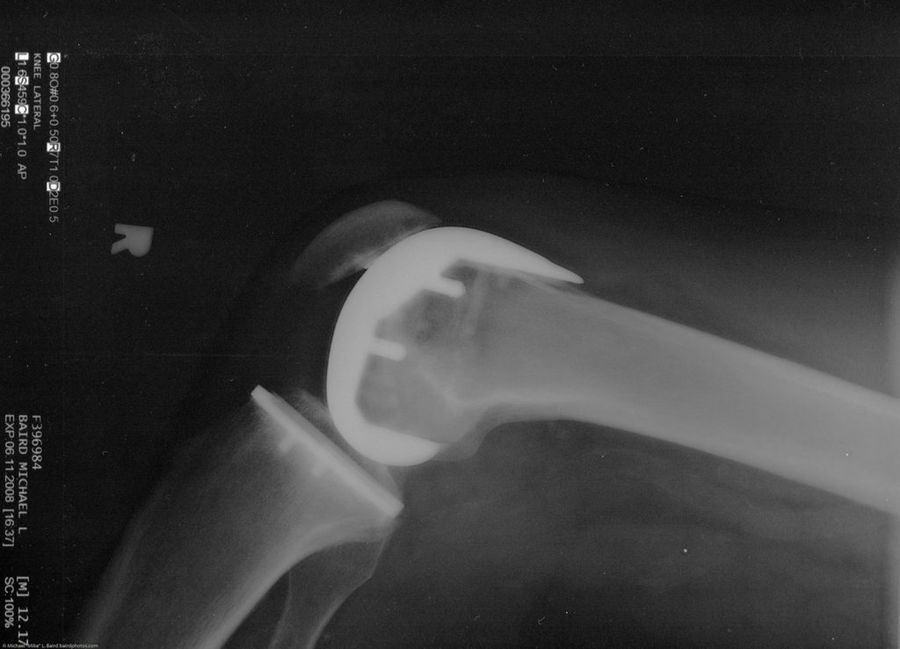

Un desgaste del cartílago articular como el que hablamos, puede ser diagnosticado por tu médico con una exploración de articulaciones o con una simple radiografía. Actualmente no existe una cura definitiva para la artrosis ni un remedio que regenere el cartílago articular. Pero existen diversos tratamientos que pueden ayudarnos a sobrellevar mejor los dolores propios de la enfermedad y también nos permiten al paciente llevar una vida prácticamente normal. Lo más importante en estos casos es que los pacientes nos enfrentemos a la situación que estamos viviendo y adaptemos nuestras actividades al nuevo estilo de vida que tenemos, más tranquilo y reposado. Nuestra vida sería entonces mejor.